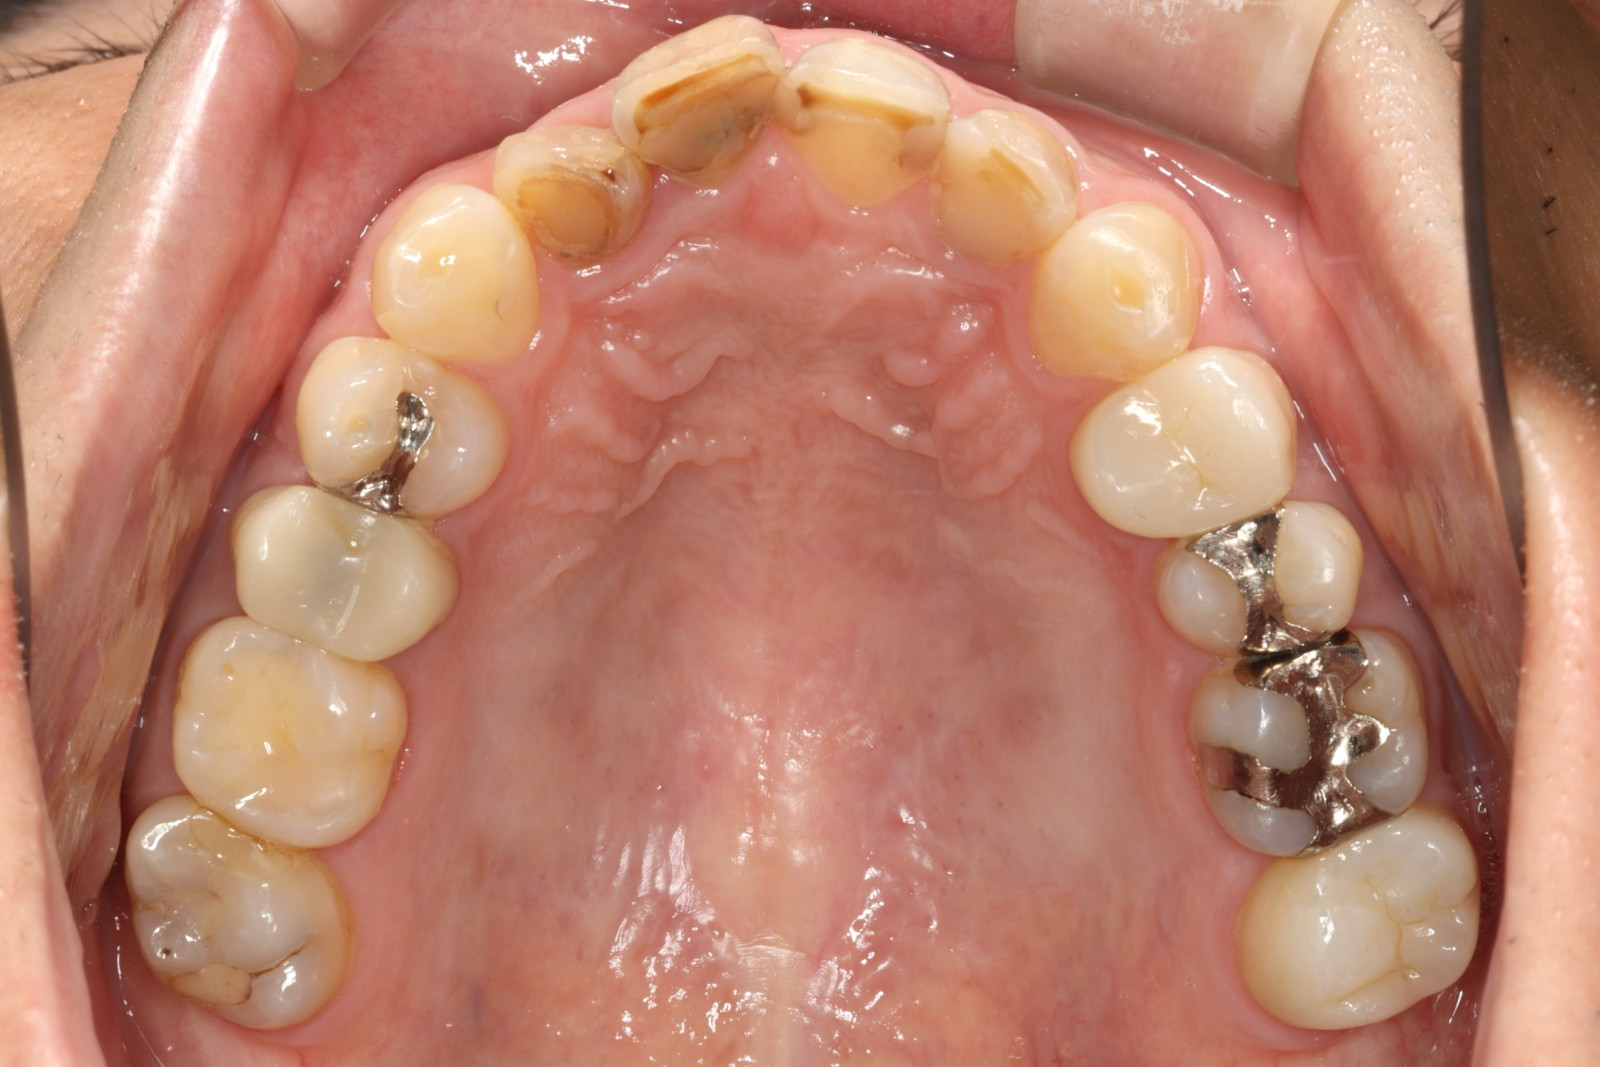

一般的に、歯並びを整える方法としては「歯列矯正」があり、歯の形や色を整える方法として

は「セラミック治療」があります。

当院では、これらを組み合わせた「セラミック矯正」を提供しています。具体的には、セラミックの被せ物を使って歯の形や色を整えながら、同時に歯並びも改善していきます。

しかし、その一方で「健康な歯を削る」必要があります。セラミックの被せ物を装着するためには、どうしても天然歯を削らなければなりません。